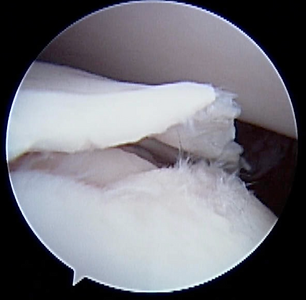

Arthroscopic image of an OCD flap.

Osteochondrosis is a disorder in which the normal process of cartilage turning into bone (endochondral ossification) is disrupted in a growing dog. When a section of this abnormal cartilage cracks or separates from the underlying bone, it forms a loose or partially attached flap — a stage called osteochondritis dissecans (OCD). This flap causes joint irritation, inflammation, and mechanical interference with movement, resulting in pain and lameness.

OCD lesions are usually visible on good-quality radiographs (X-rays), especially in typical joint locations. CT scans may be used to better define the size, shape, and exact location of the defect — helpful for surgical planning. Arthroscopy allows direct visualization of the lesion and confirmation of cartilage flap formation.